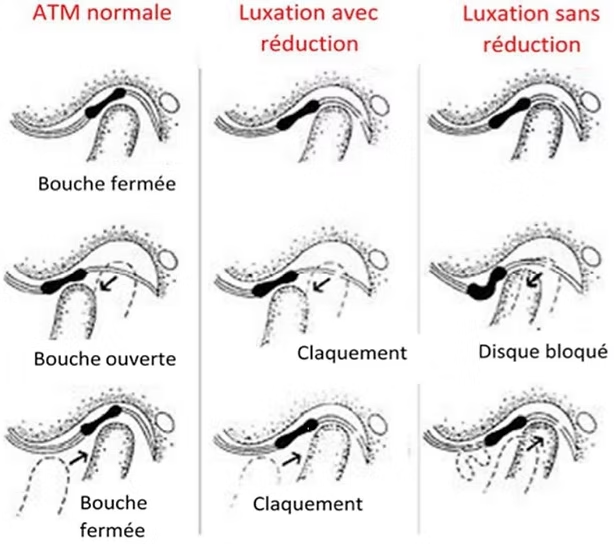

- Dysfonction temporo-mandibulaire (luxation discale, arthrose)

- Bruits dans l'articulation (claquement, crissements)

- Limitation d'ouverture de bouche

Les symptômes incluent : douleurs en avant de l'oreille, limitation d'ouverture buccale, bruits articulaires (claquements, crissements), maux de tête, douleurs cervicales associées et parfois des acouphènes. Ces symptômes peuvent être unilatéraux ou bilatéraux.